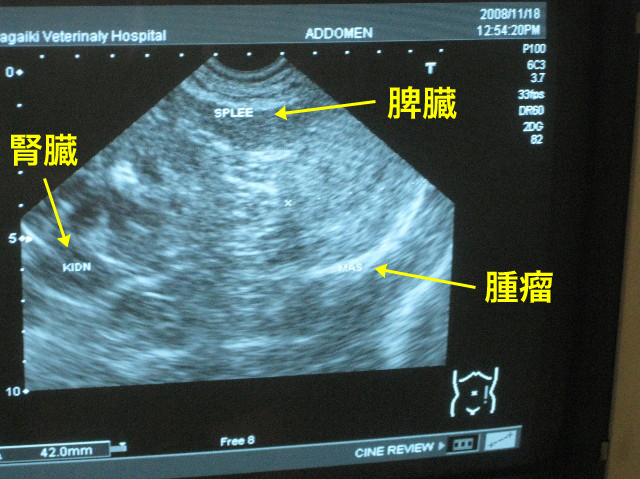

CT画像をみながら、もう一度良く説明してもらった。

それにしてもでっかい腫瘍だよね。

そんな事はわからないけれど、この後のエコーで、わりと最近できて急速に大きくなったのではないか?という雰囲気。。。

先週、先々週と2.5cmくらいだったベベちゃんの脾臓のうっ血?みたいな部分。

6日後の今日には4.3cmにも大きくなっていて先生方はびっくり。

上の黒くうつっているところが本来の正常な脾臓の組織。

CTではよくわからないけれど、うっ血と言っていた部分はもしかしたら腫瘍みたいな出っ張りかもしれない。

脾臓は血の貯蔵庫みたいなものだから、容易に一部分が倍の大きさになったり、逆に小さくなったりすることもあるらしい。

位置関係はこんな。

それぞれの臓器との境界を詳しくみてくださって、ベベの腫瘍は脾臓由来のものである可能性が高まった。